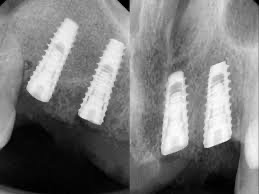

• X光或3D掃描:了解骨頭狀況,評估是否需要補骨或其他前置手術。

• 印製個人牙拖模型、拍攝根尖X光片確認植體與齒槽骨狀況、裝戴上癒合帽(局部麻醉下)